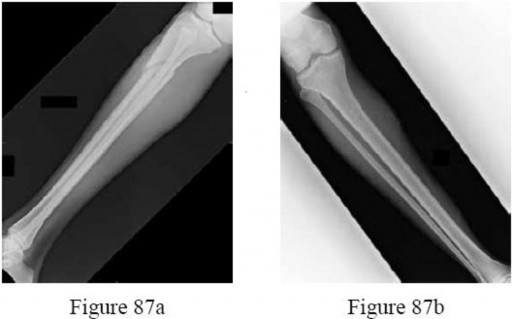

-are the radiographs of an 18-year-old pedestrian who was struck by a car. During intramedullary nailing, it is difficult to maintain proper alignment. Poller blocking screws placed in the proximal fragment at which position(s) relative to the nail can help prevent the typical deformity?